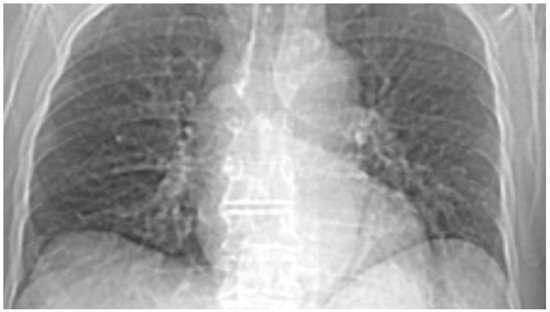

3.7. Results of Healthy Patients—A Final Comparison Using Control Data

In this subsection, we present and discuss the pulmonary CT scan of healthy lungs, which were not affected by the presence of SARS-CoV-2.

The chest radiograph of healthy lungs on which the fractal analysis was performed is shown in Figure 29a. Aside from the high-quality imaging provided by CT procedures (Figure 29a,b), the picture evaluation assured quantitative information regarding various structural features, such as the fractal dimension and lacunarity.

Figure 30 shows the 2D box-counting algorithm with the local fractal dimension calculation for the healthy-lung CT image. Figure 31 displays the 3D graphical representation of the voxels present in the CT lung image of healthy patient. Table 7 presents the calculated values for the fractal dimension and the lacunarity of the CT image evaluations for the healthy patient.

Table 7 shows the known fractal indicators, such as the fractal dimension of the CT image of the left lung, dHL = 1.6410 ± 0.3577, and lacunarity Λ = 0.0475; and the fractal dimension of the right lung, dHR = 1.6318 ± 0.3598, and lacunarity, Λ = 0.0486.

Figure 29. (a) Healthy lung image, (b) binary version, (c) mask for the left lung, (d) mask for the right lung.